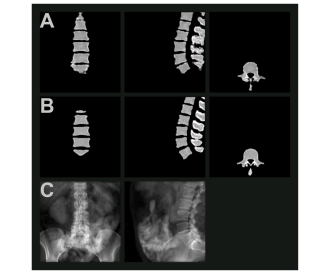

Fig. 3. Synthetic computed tomographic image based on internal validation dataset of spine from biplanar radiographs A) Synthetic CT in coronal, sagittal, and axial planes; B) Ground truth masked CT in corresponding planes; C) Input digitally reconstructed radiograph. Data sourced from Sekuboyina et al. (Sekuboyina et al., 2021), and figure derived from a model first published by us in (Zanier et al., 2024).

图3:基于双平面X光片的脊柱内部验证数据集生成的合成计算机断层扫描(CT)图像。A)冠状面、矢状面和轴面的合成CT图像;B)相应平面的真实掩模CT图像;C)输入的数字重建X光片。数据来源于塞库博伊纳等人(Sekuboyina等人,2021年),该图源自我们首次在(扎尼尔等人,2024年)中发表的模型。